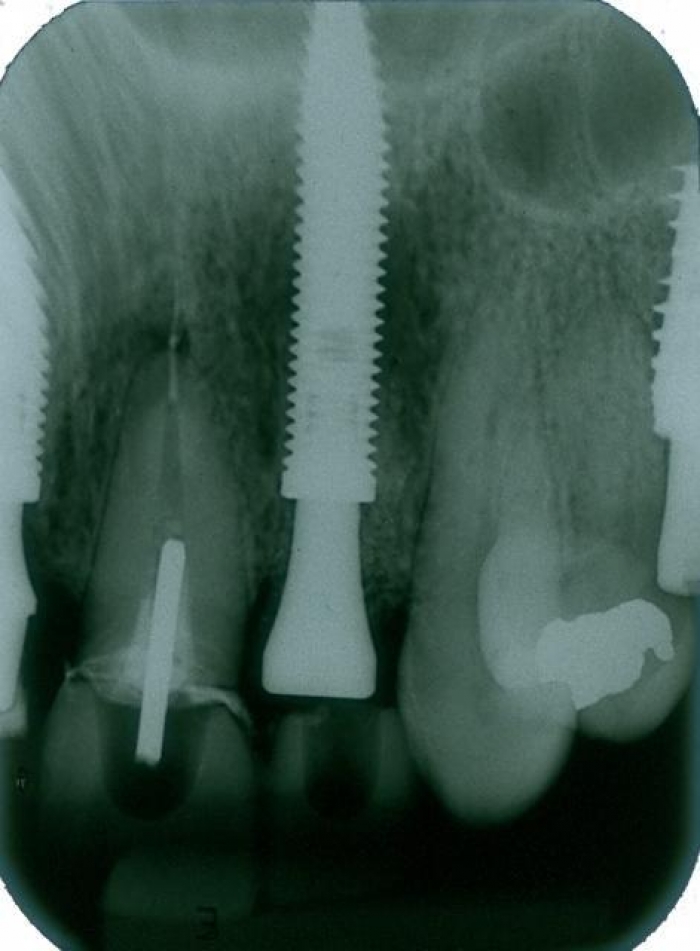

Raio X inicial

Rx após extração e implantes imediatos nos dentes 12 e 22